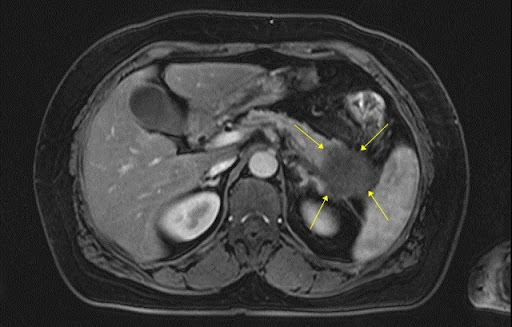

복부 CT는 X-ray(엑스레이)보다 훨씬 정밀한 영상을 찍을 수 있어서, 다양한 장기의 상태를 한눈에 볼 수 있어!

🔹 간 질환 – 지방간, 간경화, 간암 등 확인 가능

🔹 췌장염·췌장암 – 췌장에 염증이 생기거나 종양이 있는지 체크 가능

🎗 간암, 췌장암, 대장암, 신장암 등 초기 단계에서 발견 가능!

🎗 양성종양 or 악성종양(암) 판별 – 혹이 생겼다면 악성인지 양성인지 확인할 수 있음